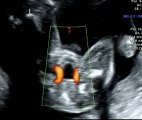

Canale atrio - ventricolare